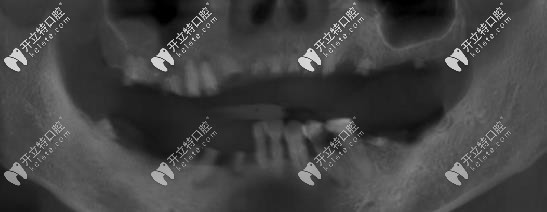

曲面斷層片

口腔情況:上半口牙全掉,下半口有5顆松動(dòng)牙,牙位已變動(dòng),曾帶過一段時(shí)間的活動(dòng)義齒。